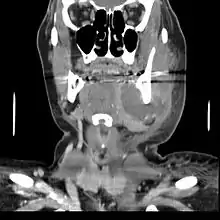

In some cases, a tooth abscess may perforate bone and start draining into the surrounding tissues creating local facial swelling. In some cases, the lymph glands in the neck will become swollen and tender in response to the infection. It may even feel like a migraine as the pain can transfer from the infected area. The pain does not normally transfer across the face, only upwards or downwards as the nerves that serve each side of the face are separate.

If left untreated, a severe tooth abscess may become large enough to perforate bone and extend into the soft tissue eventually becoming osteomyelitis and cellulitis respectively. From there it follows the path of least resistance and may spread either internally or externally. The path of the infection is influenced by such things as the location of the infected tooth and the thickness of the bone, muscle and fascia attachments.

Internal drainage is of more concern as growing infection makes space within the tissues surrounding the infection. Severe complications requiring immediate hospitalization include Ludwig's angina, which is a combination of growing infection and cellulitis which closes the airway space causing suffocation in extreme cases. Also infection can spread down the tissue spaces to the mediastinum which has significant consequences on the vital organs such as the heart. Another complication, usually from upper teeth, is a risk of sepsis traveling through pathways to which it can possibly lead to endocarditis, brain abscess (extremely rare), or meningitis (also rare).